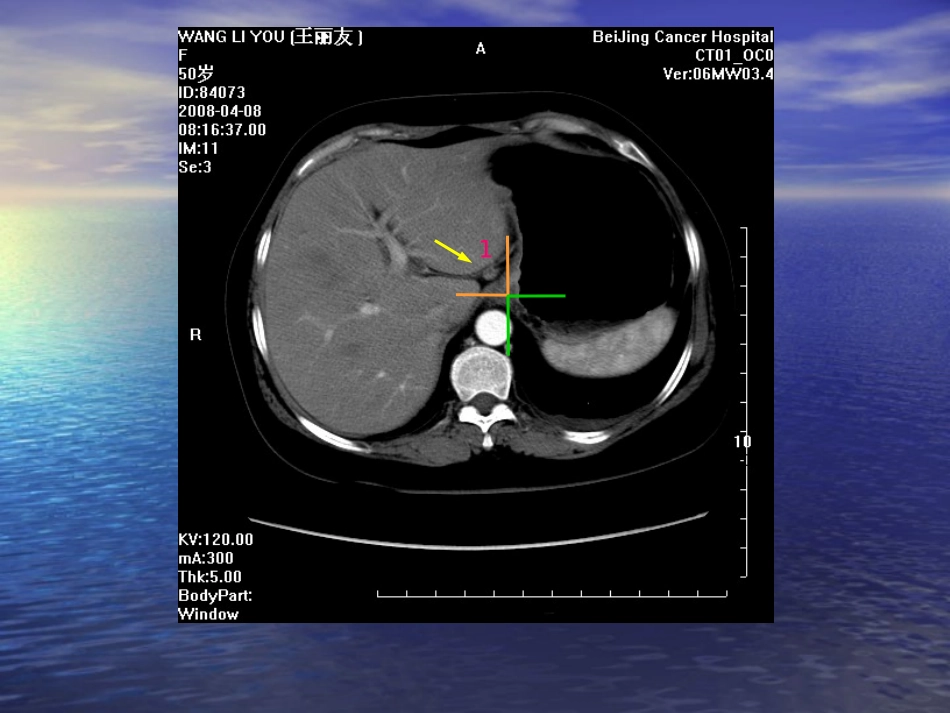

胃癌的淋巴结分组胃癌的淋巴结分组19931993年年1212版《胃癌处理规约》版《胃癌处理规约》2008.12008.111212No1贲门右腹段食管和贲门的右前方No2贲门左腹段食管和贲门的左后方No19膈下膈肌腹侧面,沿膈下动脉分布(左膈下动脉分叉以外)No20食管裂孔膈肌食管裂孔部1组No③小弯淋巴结:位于①组与之⑤间淋巴结,沿胃小弯分布,CT上位于胃前内侧壁与肝内下面之间。No④大弯淋巴结:沿胃网膜左、右动脉分布,由于卧位扫描的缘故,胃大弯与立位时相比出现转位,在CT表现上,体上部大弯的淋巴结位于胃的外、后侧壁,体下部—幽门部的淋巴结则常显示于胃外侧壁与前腹壁之间的区域。该组又分为两个亚组,沿胃网膜右动脉分布者为大弯右组(4d),沿胃网膜左动脉和胃短动脉靠近胃者为大弯左组(4s)。将位于胃短动脉靠近胃者称为(4sa),沿胃网膜左动脉分布者为(4sb)。(4s)与⑩脾门淋巴结的界限是胃网膜左动脉向胃大弯发出的第1支,正位于此支上者为(4sb)。3组4组No③小弯淋巴结:位于①组与之⑤间淋巴结,沿胃小弯分布,CT上位于胃前内侧壁与肝内下面之间。No④大弯淋巴结:沿胃网膜左、右动脉分布,由于卧位扫描的缘故,胃大弯与立位时相比出现转位,在CT表现上,体上部大弯的淋巴结位于胃的外、后侧壁,体下部—幽门部的淋巴结则常显示于胃外侧壁与前腹壁之间的区域。该组又分为两个亚组,沿胃网膜右动脉分布者为大弯右组(4d),沿胃网膜左动脉和胃短动脉靠近胃者为大弯左组(4s)。将位于胃短动脉靠近胃者称为(4sa),沿胃网膜左动脉分布者为(4sb)。(4s)与⑩脾门淋巴结的界限是胃网膜左动脉向胃大弯发出的第1支,正位于此支上者为(4sb)。3组4组No7胃左动脉干沿胃左动脉根部至上行支的分支部分布No8肝总动脉干肝总动脉前面和上缘8a,后面8pNo12肝十二指肠韧带内肝总动脉上方层面沿肝门脉、胆管分布至肝门部7组12组4组3组No9腹腔动脉周围胃左动脉根部、肝总动脉根部、脾动脉根部No10脾门胰尾末端与脾门之间No11脾动脉干沿脾动脉分布脾动脉肝总动脉腹腔干3组脾动脉11组肝总动脉8组No8肝总动脉干肝总动脉前面和上缘8a,后面8pNo11脾动脉干沿脾动脉分布11组肠系膜上动脉腹腔干No③小弯淋巴结:位于①组与之⑤间淋巴结,沿胃小弯分布,CT上位于胃前内侧壁与肝内下面之间。No④大弯淋巴结:沿胃网膜左、右动脉分布,由于卧位扫描的缘故,胃大弯与立位时相比出现转位,在CT表现上,体上部大弯的淋巴结位于胃的外、后侧壁,体下部—幽门部的淋巴结则常显示于胃外侧壁与前腹壁之间的区域。该组又分为两个亚组,沿胃网膜右动脉分布者为大弯右组(4d),沿胃网膜左动脉和胃短动脉靠近胃者为大弯左组(4s)。将位于胃短动脉靠近胃者称为(4sa),沿胃网膜左动脉分布者为(4sb)。(4s)与⑩脾门淋巴结的界限是胃网膜左动脉向胃大弯发出的第1支,正位于此支上者为(4sb)。4组3组脾门No17胰头前与13对应,位于胰头前方No10脾门胰尾末端与脾门之间No13胰头后门静脉左缘外侧,胰腺上缘下方的胰头后13组幽门No14肠系膜根部沿肠系膜上静脉分布,胰腺下缘下方No18胰下胰体胰尾交界部下缘No16主动脉周围左肾静脉下缘为界分a,b区,